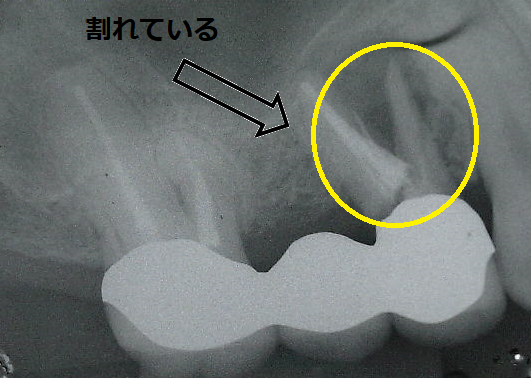

左のX線の矢印で示してある歯が割れていたので、一旦歯を抜いてきれいにしました。